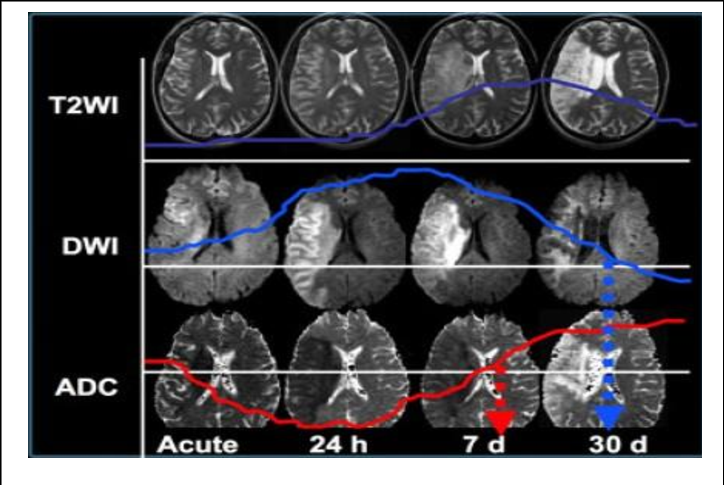

Características de RM de craneo T2:

A

• Liquido y grasa hiperintensas

• Sustancia blanca es mas obscura

Evaluación de la difusión:

• Si se encuentra hiperintenso en todos ya es muy tardío